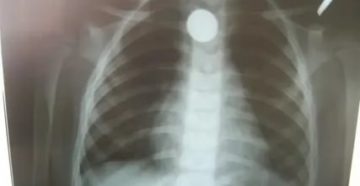

Инородное тело в бронхах: симптомы и лечение Особую разновидность патологии респираторного тракта составляют инородные тела….